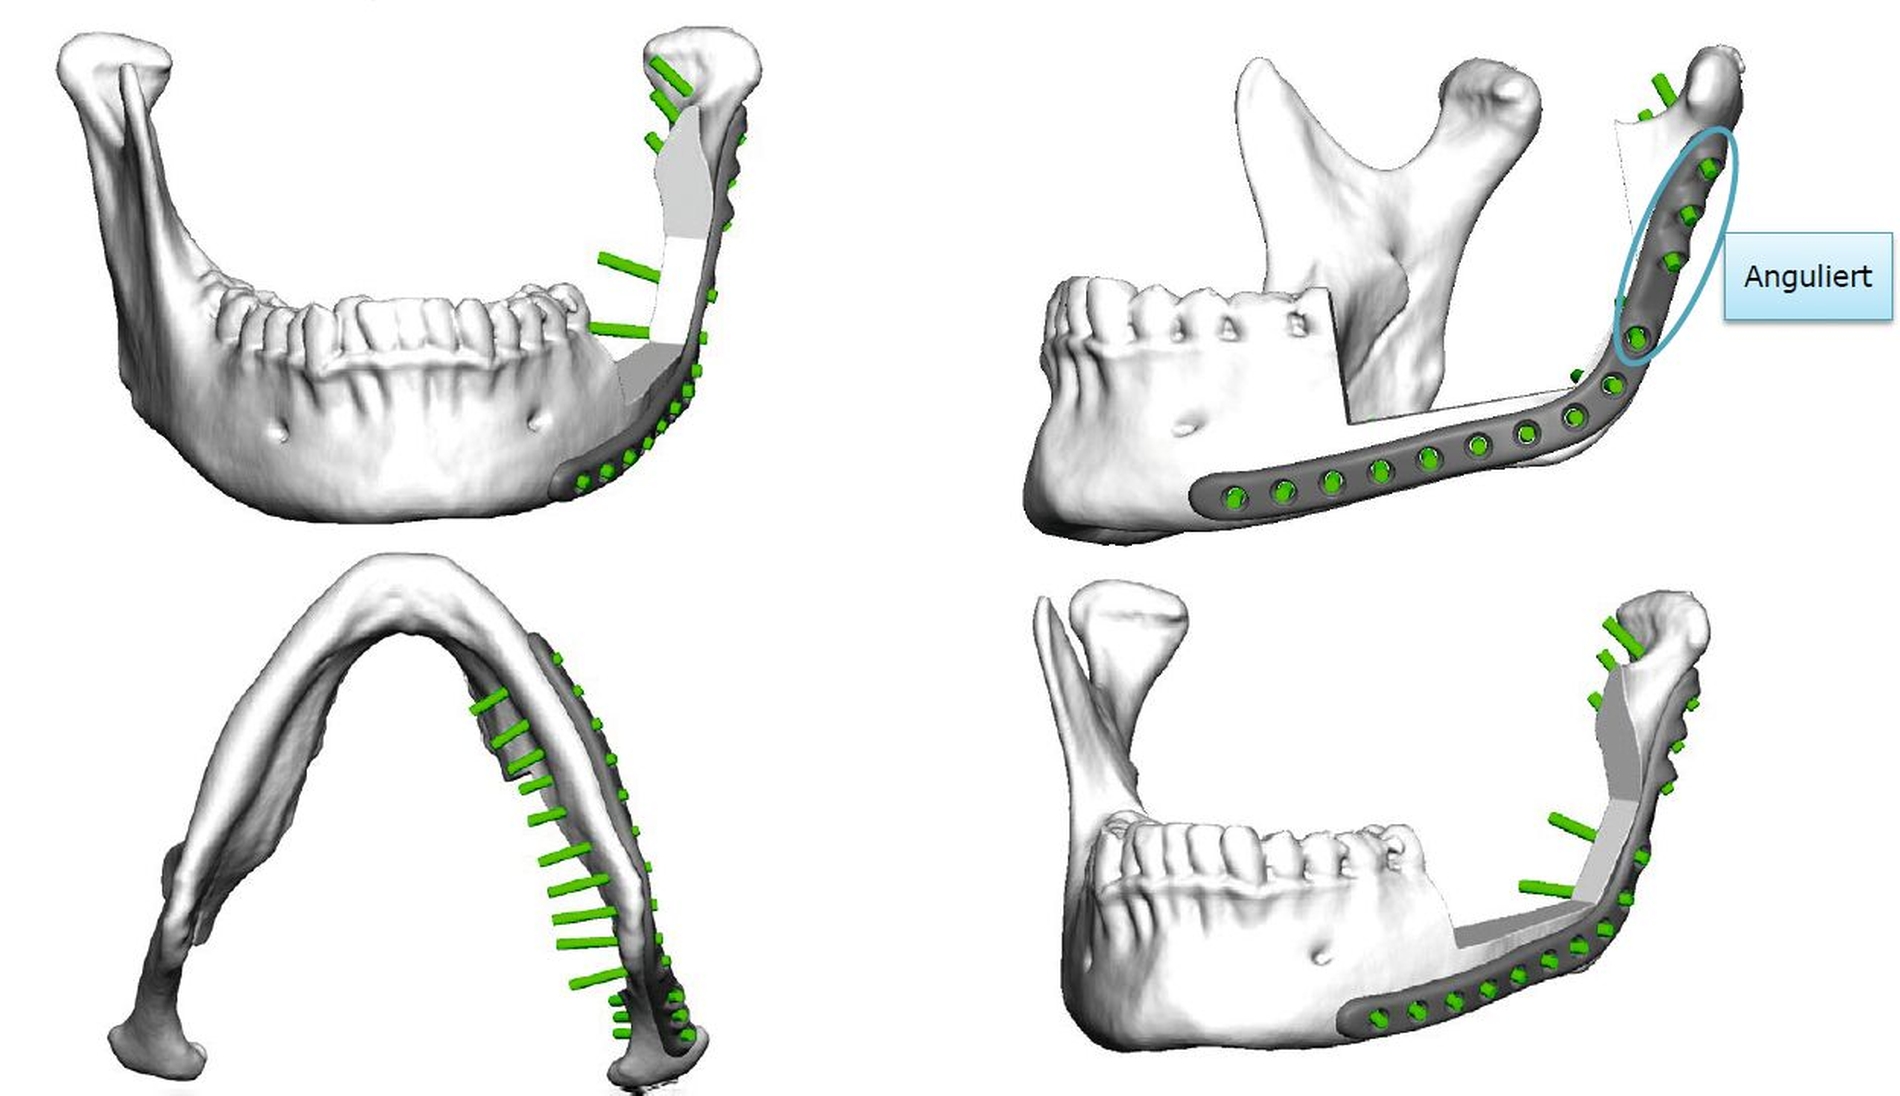

Die Therapie der Wahl bei Odontomen stellt die Enukleation dar. Aufgrund der Ausdehnung der Raumforderung und der Nähe zum N. alveolaris inf. entschieden wir uns dazu, eine 3-D-virtuelle Operationsplanung durchzuführen. Anhand des zuvor angefertigten Computertomogramms erstellten wir eine Resektionsschablone im CAD/CAM-Verfahren, um so eine Kontinuitätserhaltung zu garantieren. Weiterhin erfolgte die CAD/CAM-Fertigung einer Rekonstruktionsosteosyntheseplatte (Abbildungen 2 bis 4).

Der Eingriff erfolgte über einen submandibulären Zugang in Intubationsnarkose. Intraoperativ zeigte sich eine starke Auftreibung der Kortikalis des Ramus ascendens. Der aufsteigende Unterkieferast wurde nahezu vollständig subperiostal dargestellt, das anhängende Weichgewebe mit dem Raspatorium gelöst. Die Resektionsschablone wurde eingebracht und die geplante Schnittführung mit dem Piezo markiert.

Der N. alveolaris inf. wurde zurück in sein ursprüngliches Bett verlagert und mit Fibrinkleber bedeckt. Nun erst wurde die Rekonstruktionsosteosyntheseplatte eingebracht und entsprechend der Planung verschraubt. Zur Augmentation des resektionsbedingten Knochenverlusts erfolgte die Transplantation zweier kortikospongiöser Beckenkammspäne von der rechten Spina iliaca anterior in den Defekt. Die Knochenblöcke wurden mit einer konventionellen Osteosyntheseplatte fixiert (Abbildung 6).

Die computerassistierte Chirurgie ermöglicht eine präzise, 3-D-unterstützte Operationsplanung und kann im Fall von ausgedehnten Befunden eine vorhersagbar durchzuführende Operation ermöglichen. Im vorliegenden Fall konnte das Ausmaß der Resektion auf ein Minimum beschränkt werden; somit konnten sowohl die Unterkieferkontinuität als auch die Sensibilität des N. alveolaris inf. erhalten werden.

Durch die Anfertigung einer CAD/CAM-gefertigten Rekonstruktionsplatte kann eine ideale Positionierung und Passung des Osteosynthesematerials garantiert werden, was die Operationszeit verkürzen und postoperativen Komplikationen, zum Beispiel einer Plattenexposition, durch mangelhafte Passung entgegenwirken kann.